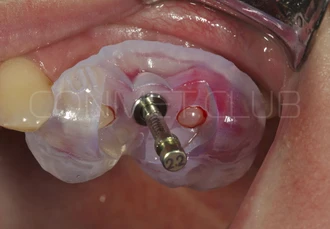

Обязательным условием работы с направляющими шаблонами является проверка точности посадки позиционирующего шаблона на апроксимальные зубы. Посадка не должна быть чрезмерно плотной и шаблон должен располагаться на зубах без баланса.

Препарирование ложа производится через слизистую оболочку, без отслаивания лоскутов, в таком случае контроль глубины препарирования следует проводить с учётом толщины слизистой оболочки и высоты направляющей втулки.

Имплантат устанавливается в подготовленное ложе. Так как не производится широкого откидывания слизисто надкостничных лоскутов и операция проводится через маленькое перфорационное отверстие, кровоточивость и сама операционная травма - минимальные.

После установки имплантата Конмет,  на период интеграции (6-8 недель), фиксируется винт заглушка. В подобных случаях швы никогда не накладываются, а пефорационное отверстие в слизистой оболочке закрывается дентальным Солкосерилом.